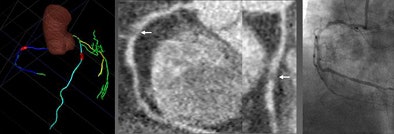

| The investigational CAD algorithm automatically tracks and segments the coronary tree, extracting vessel centerlines and labeling them before performing automated stenosis detection and marking of target vessels. All images courtesy of Dr. Joseph Schoepf. |

| Image shows 64-slice coronary CTA in a 61-year-old woman with body mass index greater than 40kg/m2 and atypical chest pain. CAD detected significant stenosis caused by noncalcified plaque in the proximal right coronary artery confirmed by invasive catheter angiography. The lesion was missed by three of five readers, due to high image noise. |